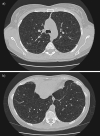

High-resolution computed tomography scans of the chest in a patient with histological diagnosis of lymphangioleiomyomatosis. Round shaped, thin-walled cysts are distributed diffusely throughout the lungs (a) without sparing of lung bases (b).